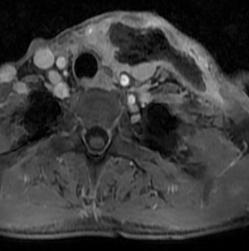

术后,积极使用全身应用广谱抗生素联合抗厌氧菌抗生素抗感染、营养支持、配合中药外敷内服、改良负压引流+积极换药等治疗,经过医护团队的积极救治和悉心照料,张大姐已度过了危险期,咽喉会厌脓肿及颈部脓肿逐渐缩小闭合,感染病情明显好转,引流管已拔除。

(术后14天颈部MRI复查病情)